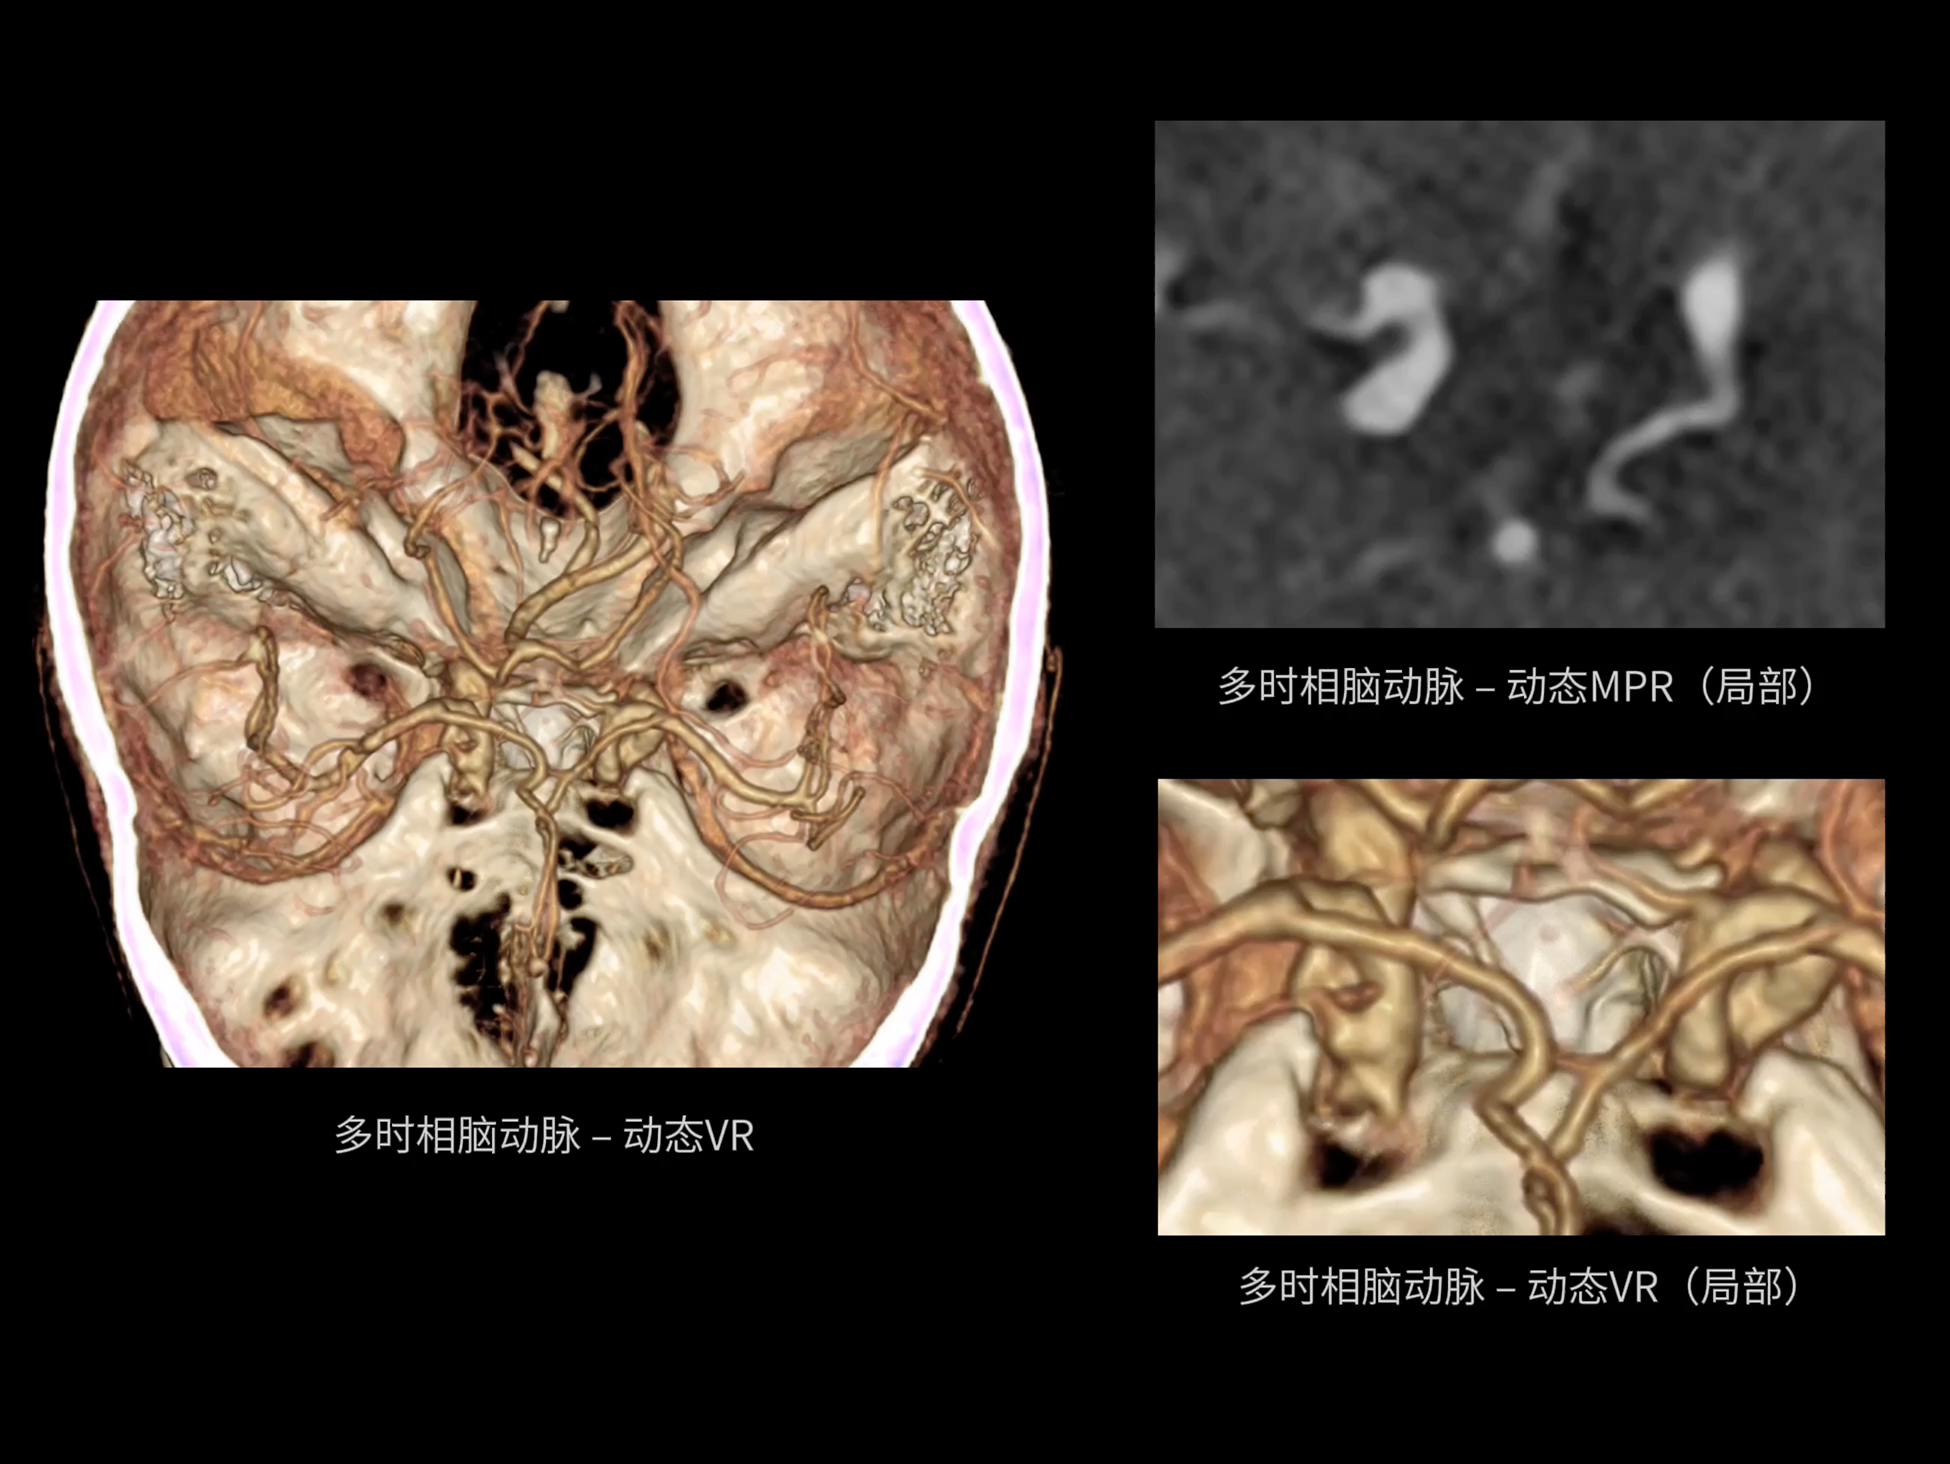

成就器官级动态时间分辨率

uCT SiriuX® 在双源扫描模式基础上,全面优化机架设计,成功克服系统转动惯量及高离心力挑战,进一步提升转速,实现高达 63ms 的超高物理时间分辨率。

uCT SiriuX® 以16cm超宽Z轴覆盖,使超高时间分辨率应用于完整器官成像。无论是心脏搏动还是关节运动,整个目标区域可在同一瞬时被完整、清晰地捕捉,彻底消除时序误差,实现从“局部瞬间”到“全器官瞬时”的成像跨越。

瞬息捕捉

全器官同步